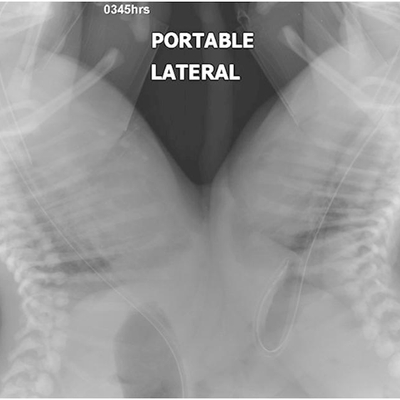

Click on an image below to view more info.